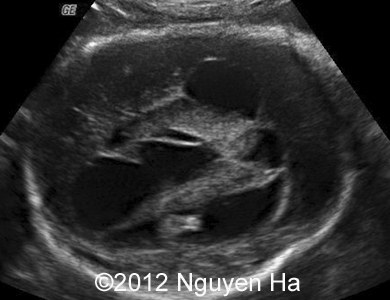

A 30-year-old woman (G1P0), with unremarkable family history, presented to our unit at 36 weeks of her pregnancy. She did not undergo any previous screening tests. Our examination (and repeated scan after four days) revealed following findings:

A 30-year-old woman (G1P0), with unremarkable family history, presented to our unit at 36 weeks of her pregnancy. She did not undergo any previous screening tests. Our examination revealed unilateral hypoechoic inhomogeneous mass within cerebral parenchyma. Our initial diagnosis was teratoma, but repeated exam after four days showed structural changes and different echogenicity of the mass and so our final diagnosis was cerebral hemorrhage. The findings were confirmed by MRI scan.

Figure 1-7: 36 wekks of pregnancy.